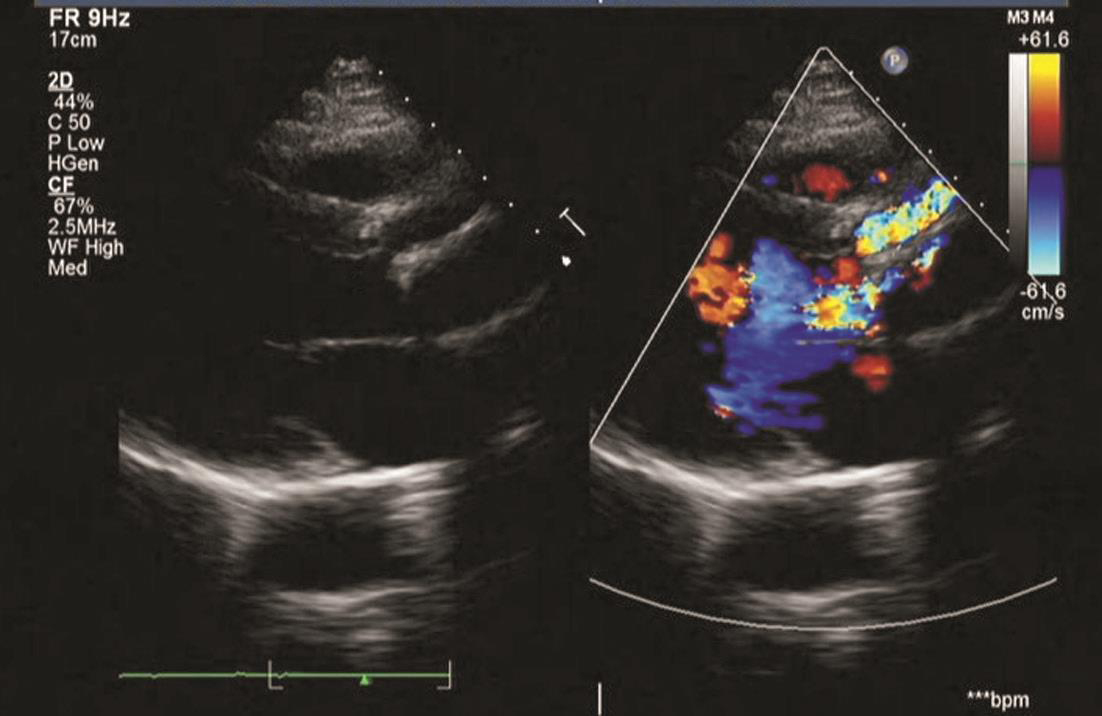

既往检查结果如下:2012年10月,心脏彩超示人工主动脉瓣及管道与主动脉根部前缘可见约直径0.68cm的漏口(图4);左心造影示环主动脉根部假性动脉瘤,漏口位于左前方可能性大;胸主动脉CTA示主动脉瓣区升主动脉根部术区造影剂外渗(图5)。2013年11月,复查胸主动脉CTA提示升主动脉漏口较前明显增大(直径约1.2cm)。2015年5月,心脏彩超示人工主动脉与主动脉前壁间血流信号,考虑术后再次出现瓣周漏(图6);胸主动脉CTA示主动脉根部造影剂漏出,形成一假性动脉瘤,升主动脉上部部分管壁增厚伴溃疡(图7);实验室检查示血沉35mm/h、C反应蛋白35.2mg/dl,抗链球菌溶血素86U/ml,降钙素原正常。

图6 心脏彩超(2015-05)

(四)临床转归

治疗后,患者胸闷、气促好转,口腔溃疡消失,血沉及C反应蛋白水平降至正常,4周后甲泼尼龙逐渐减量至8mg/d并维持,英夫利昔单抗共应用12次。随访至2017年3月,患者病情稳定,复查心脏彩超示瓣周漏口无扩大(图9)。

图9 心脏彩超(2017-03)